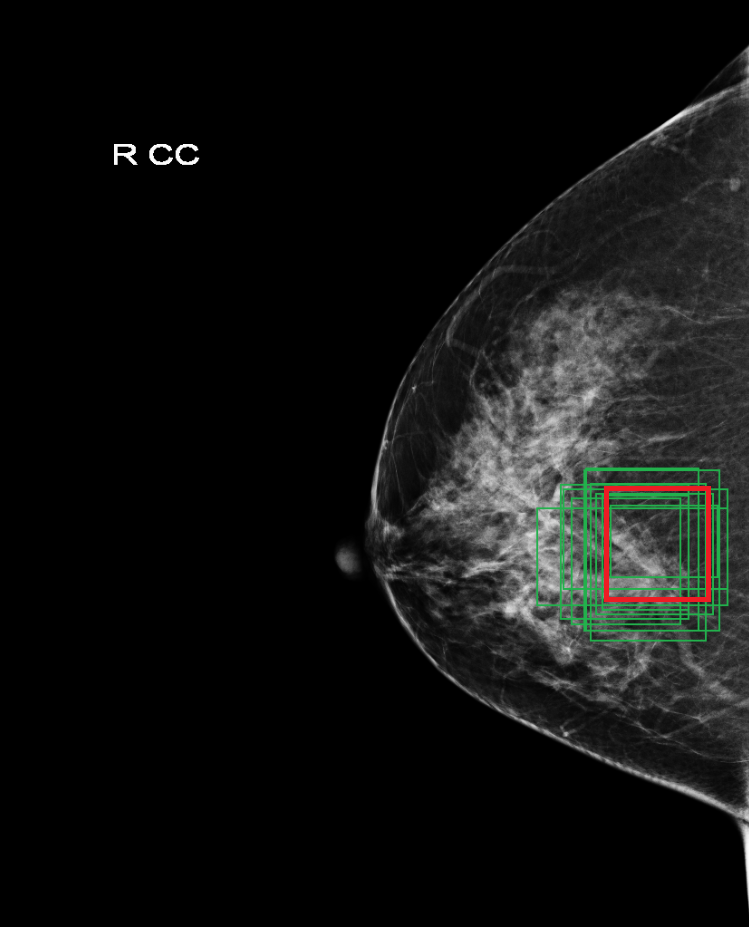

However, the negative image does not contain any annotation, which means all anchors are negative including those anchors contain suspected targets. It is possible to optimize the loss functions of all anchors, but this will bias towards normal regions since they are dominate. Those suspected target region still likely to be recognized as positive since they don’t have enough chance to be trained. To deal with this issue, we propose a top likelihood loss by ranking the scores of all anchors and sample the top 256 anchors to compute the loss function. The anchors with top scores should be more representative for those suspected target regions as the training goes on. On the other hand, as long as those top score anchors get minimized, all anchors are optimized towards negative at the same time. Figure.3 shows the sampled anchors for the positive and negative images within a single mini-batch when training the RPN, all sampled anchors are around the suspected target region for the negative image. The top likelihood loss is defined:

Deep learning object detection algorithm has been widely used in the task of classifying or detecting objects of natural images [3] and [8], and are receiving more and more attentions on its usage in medical image analysis. However, current object detection tasks are all based on the data annotated with object classes and their bounding boxes, those images which are not considered during labeling may contain regions or objects that are similar to the target ones, and may be misclassified in the testing stage. This phenomenon is critical in medical image analysis. For example, as shown in Fig.(1), a healthy mammography may contain benign or normal regions whose features are very similar to a malignant lesion. On the other hand, when doctors perform labeling, they usually search for medical records of patients that are diagnosed as cancer first, and only selected samples are labeled and used for training. As a result, those healthy samples that contain suspected malignant regions are likely to be classified as malignant.

In the following, we define a mammography with malignant lesions as a positive image, and those malignant lesions as positive targets or targets. All the other mammography are defined as negative images, including those images contain benign or normal regions that are highly suspect to be malignant(as shown in Fig.(1)). And without loss of generality, we called those highly suspected malignant regions as suspected target regions. Within the datasets we used, all the positive targets are annotated with bounding boxes to indicate their precise locations and all the negative images do not have any annotation.